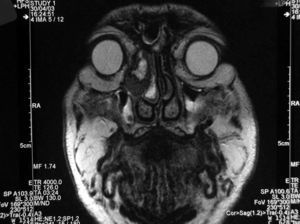

Fig. 3.--Resonancia magnética realizada tras la resección parcial del tumor. Se muestra un plano axial, secuencia potenciada en T1 con saturación grasa y tras administración de contraste paramagnético. La tumoración de la órbita derecha muestra un realce intenso y homogéneo.

Se llevó a cabo una exéresis parcial de la lesión con fines diagnósticos y posteriormente se realizó una RM, que mostró (figs. 3 y 4) una mínima infiltración de la grasa orbitaria adyacente a la tumoración y descartó la afectación de la musculatura extrínseca ocular.